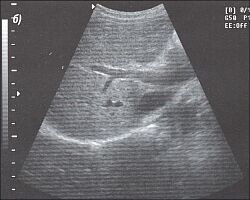

5.Техника получения поперечного среза печени. Поперечный срез печени может быть получен поворотом датчика на 90° от продольного положения и проведением его через печень (рис. 9). Эти срезы значительно помогают при оценке дилатации внутрипеченочных желчных протоков, которая отчетливо видна на поперечных срезах правой доли.

|

Заканчиваем абдоминальную ультрасонографию печени, устанавливая датчик в 7-10 межреберье для исследования свода правой доли печени, который порой не удается ясно визуализировать, особенно у тучных больных. Кроме того, межреберный доступ может помочь при осмотре сосудов и желчного пузыря.